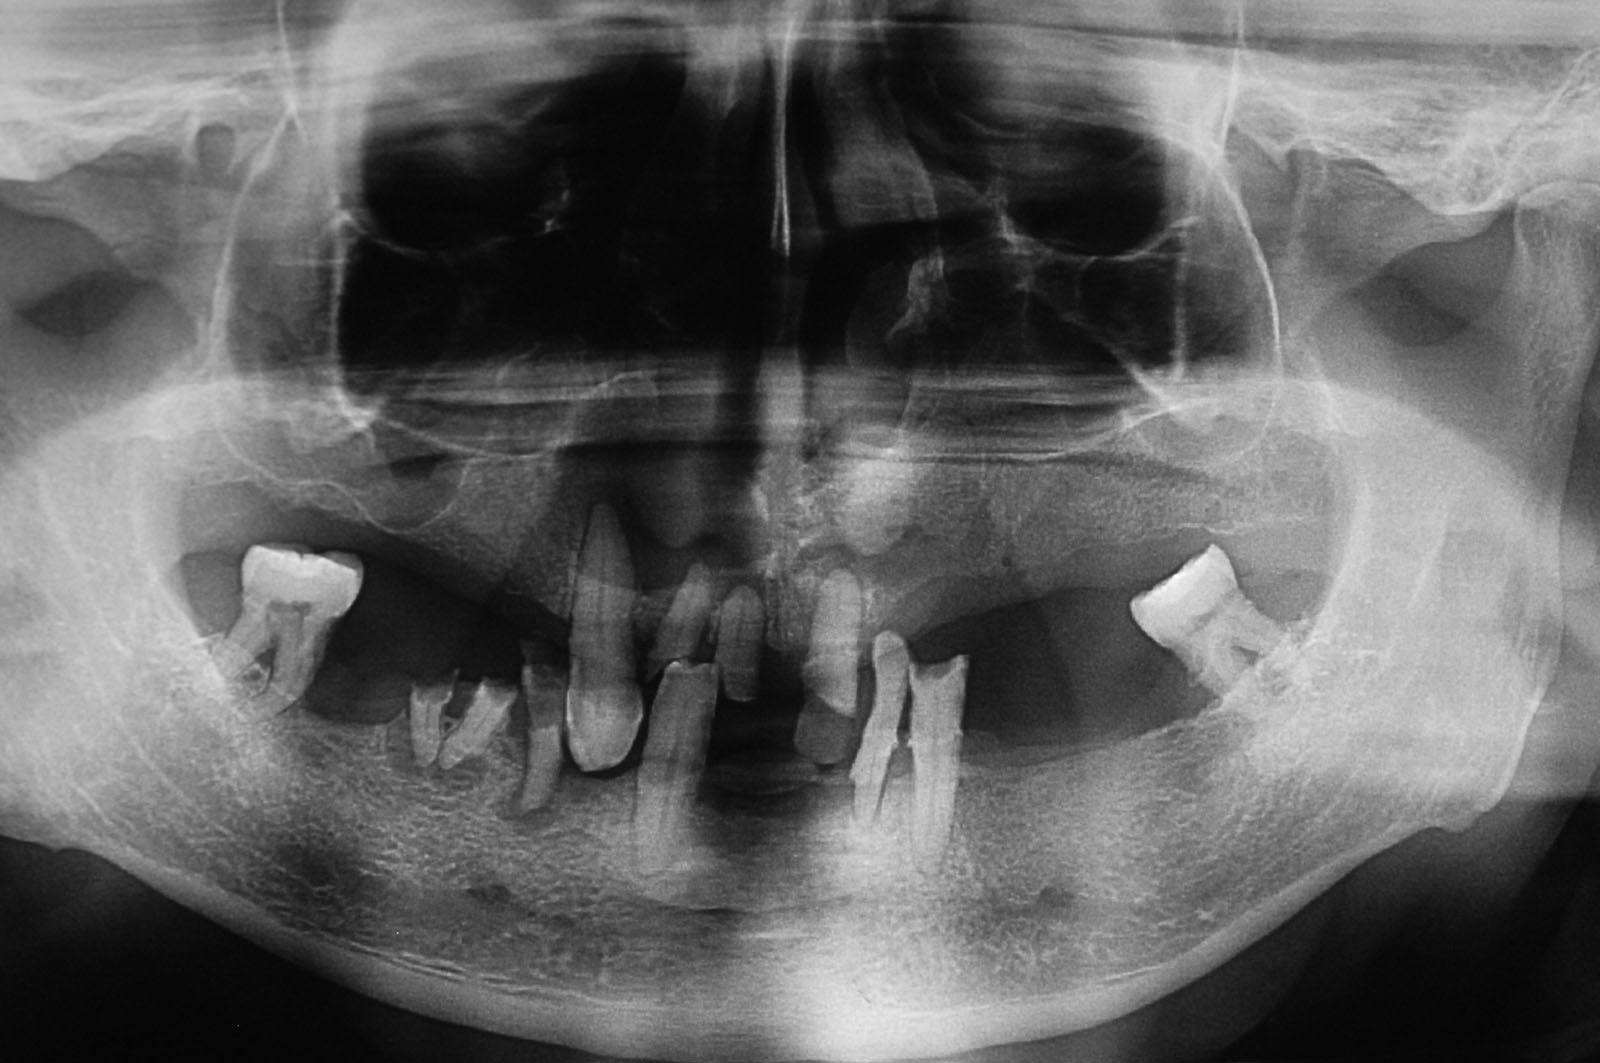

Wizytę w gabinecie stomatologicznym należy zacząć od wykonania diagnostyki. Dokonujemy tego poprzez badanie kliniczne pacjenta i wywiad lekarski oraz wykonujemy zdjęcie panoramiczne (OPG, potocznie panorama). Pozwala ono na obiektywną ocenę stanu uzębienia, przyzębia, kości szczęk i żuchwy, stanowi pełny panoramiczny obraz interesujących nas obszarów.